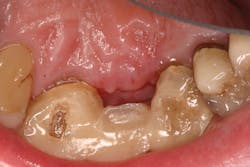

In most instances if the incision lines open and the flap tissue dehisces, a watch-and-wait approach is advisable if the graft and issue are not infected. Typically, the exposed area will have junctional epithelium granulate in it and tissue coverage will occur. This usually takes a longer time and more oversight compared with areas of primary intention (flaps are approximated and closed).

- Antiseptic mouthrinse. StellaLife has been shown to assist in tissue healing and prevent possible infections in areas of open wounds in multiple case series (figures 3–9).1